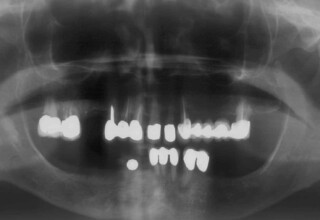

Full mouth prosthetic reconstruction on implants with a different approach on upper and lower jaw

Lower jaw: extractions, direct implant placement and immediate loading (same day) with a transitional bridge.

Upper jaw: Sequential extractions, sequential implant placement and gradual incorporation in the temporary bridge so that the patient was never left without fixed teeth. The aim of the above approach was to have the patient in continuous functional and aesthetic reconstruction, without immediate loading due to anatomical restrictions. Old smiling photos of the patient were used because the natural shape of the teeth was completely lost due to repetitive prosthetic attempts. Tooth relationship and teeth-lip support was transferred to the temporary restorations. Two different transitional bridges were needed to fully estimate phonetics, mastication and esthetics. After the necessary adjustments were finalized, the temporary bridge was used as a guide for the permanent bridges.

Initial